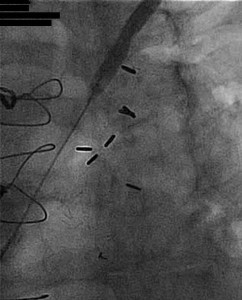

A 57-year-old diabetic woman with a history of three-vessel coronary bypass grafting presented with unstable angina in the form of chest pain occurring at rest. Stress PET-CT showed a dense reversible anterior wall defect and she was referred for urgent cardiac catheterization. Cardiac catheterization was performed via a left radial artery approach. Angiography revealed a patent LIMA-LAD, saphenous vein grafts to the right coronary artery and saphenous vein graft to the ramus intermedius. An 80{8ceaa46882e4d49283ff23b35262537230ad541262f55a031ead545e66522058} stenosis of the left subclavian artery was noted (Figure 1) and was associated with a 25 mmHg pressure gradient: